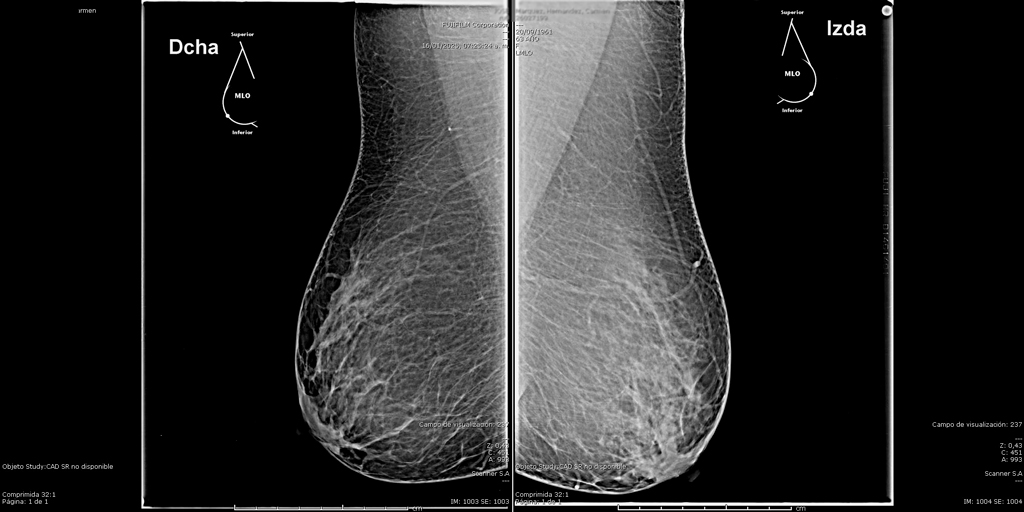

La mamografía es un estudio de diagnóstico por imagen que utiliza bajas dosis de rayos X para obtener imágenes detalladas del tejido mamario. Es una herramienta fundamental para la detección temprana del cáncer de mama y otras patologías mamarias, incluso antes de que sean evidentes al tacto o generen síntomas. Su uso regular en controles preventivos permite salvar vidas al facilitar diagnósticos oportunos y tratamientos más efectivos.

En SCANNER S.A, nuestros equipos digitalizados permiten detectar cambios mínimos en el tejido mamario con alta claridad, permitiendo asi tener un diagnostico preciso y entregar unos resultados reales a nuestros pacientes.